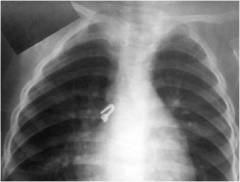

Обзорная рентгенограмма органов грудной клетки ребенка:Крючок от одежды в бронхах.

Если ребенок поперхнулся, это облегчает ситуацию, но иногда момент попадания инородного тела остается незамеченным. Мелкие неметаллические предметы сложно диагностировать, так как они могут не отображаться на рентгене, а симптомы могут напоминать пневмонию. В таких случаях бронхоскопия необходима для выявления и удаления инородного тела.

Серьезные осложнения при несвоевременном удалении инородного тела:

- асфиксия или удушение;

- нагноение бронха;

- абсцесс легкого;

- ателектаз доли легкого;

- эмфизема — может привести к разрыву легочной ткани и пневмотораксу;

- сепсис — заражение крови из очага нагноения.